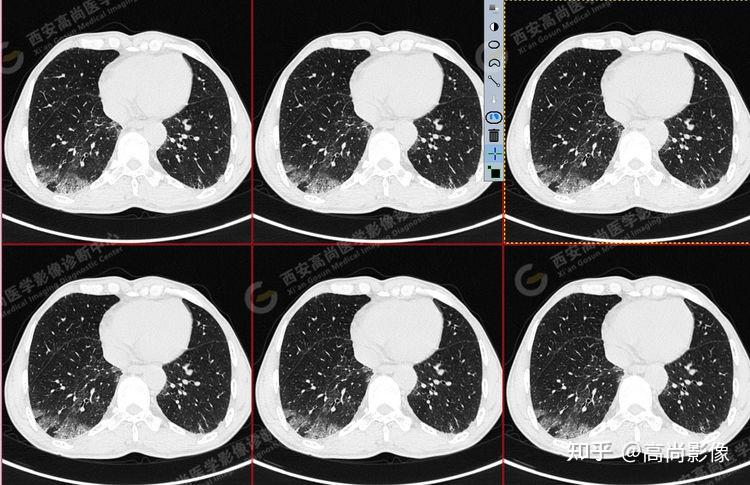

pet/ct病例—肺粘液腺癌,历经3年余终确诊【西安高尚医学影像诊断中心